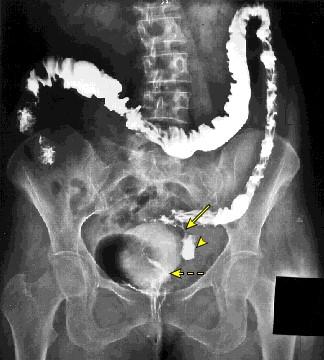

При воспалительных процессах в каком-либо участке толстой кишки окружающие органы стремятся изолировать этот участок от свободной брюшной полости. Это приводит к образованию воспалительных инфильтратов, которые захватывают не только измененный участок толстой кишки, но и прилегающие петли тонкой кишки, мочевой пузырь, матку у женщин. В 17% случаев таких инфильтратов формируется патологическое сообщение между органами, называемое свищем.

Лечение свищей исключительно хирургическое и включает резекцию затронутых органов с последующей реконструкцией.

Рисунок 3. Рентгеновский снимок — свищ между толстой кишкой и мочевым пузырем.